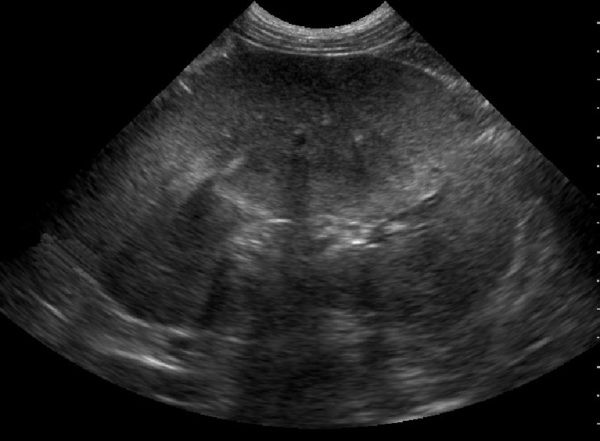

Ultrasound depicting a pancreas.

Pancreas